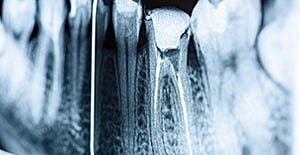

Teeth that have decay and disease in the root of the tooth will need root canal therapy to be saved and to restore health to the mouth. Root canal therapy is virtually painless, is a routine and quick procedure, and restores function to a pain-free tooth.